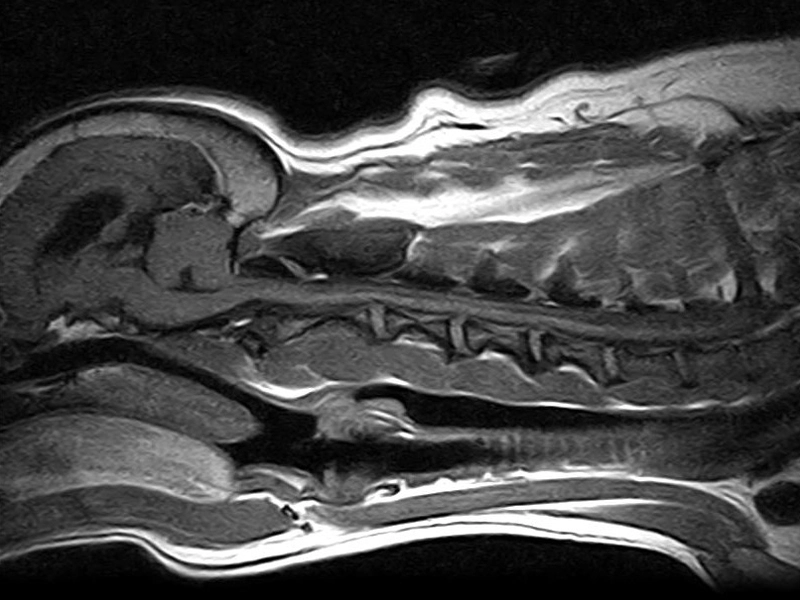

Vet-MR Grande - FSE T2 Sagittale Ernia discale cervicale C4 C5 C6 cane